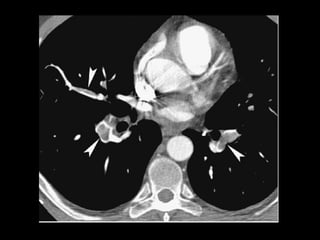

EMBOLIA PULMONAR

 A angio TC é o exame de escolha para o diagnóstico de

TEP. Apresenta como vantagens : velocidade de

realização, exclusão de outros diagnósticos e detecção

de TVP quando associado a venografia TC. Sua grande

desvantagem é a exposição a maior carga de radiação.